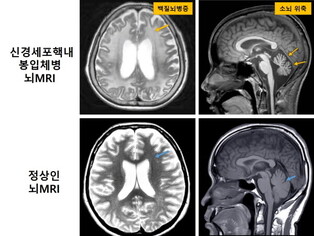

희귀 신경질환 신경세포핵내봉입체병, 빅데이터로 진단 해결 실마리 찾아

[mdtoday=이재혁 기자] 19세 환자 A씨는 9살부터 운동기능이 퇴행하면서 보행장애, 실조증과 같은 신경학적 증상을 앓았다. MRI에서 백질뇌병증과 소뇌 위축 소견이 나타났지만, 유전자 진단이 어려워 병명은 알 수 없었다. 그러 ...